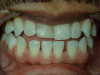

Cosmetic